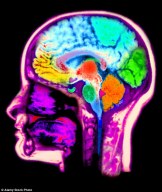

Out walking the dog I felt fuzzy headed, vision even more blurry than usual, unable to walk in a straight line, slurred speech. No drink taken. Transient ischaemic attack (ministroke) thought I as I was lumbering about. Or brain tumour, or cerebellar disease, or inner ear disease.

A&E was quiet. I was tended with efficiency and good humour. I was given a mask and learnt that nobody knows how to stop them steaming up your specs. ECG normal, head CT normal, BP 135/75 – beat that, suckers, given the amount of salt and butter I consume.

There’s an MRI next week and they mentioned continuous ambulatory heart monitoring. But I feel as if I’ll be wasting their time. I’ve no idea what caused the symptoms, and they don’t fit into any recognised disease pattern.